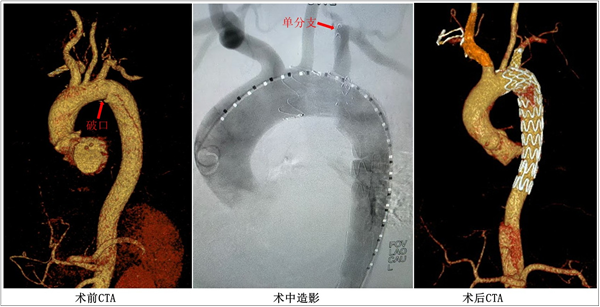

患者蔡先生主动脉CTA检查情况

舒畅教授主刀,李鑫教授、黎明副教授、王伦常主治医师和朱凡医师等团队成员共同为患者实施了这一开创性手术,精准地将该覆膜支架系统输送至病变位置,并利用其预置通路搭建了重建左锁骨下动脉的“生命轨道”。术后造影及CTA显示:主动脉夹层破口被完全封堵,假腔消失,主动脉真腔及左锁骨下动脉血流通畅,完美实现了主动脉弓的解剖重建。